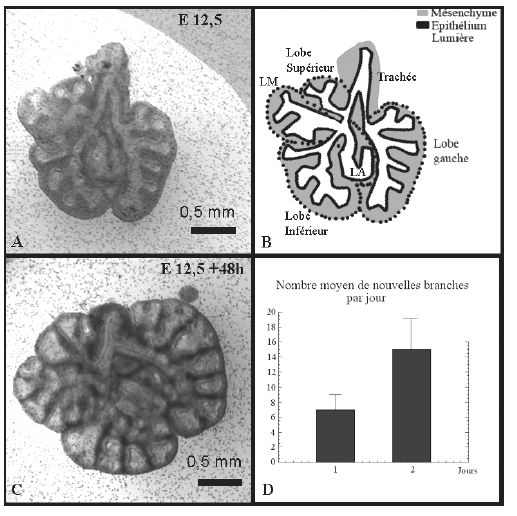

| Les effets morphologiques "directs" sont très visibles : le nombre de branches croît beaucoup plus vite dans un poumon obstrué (tel que le liquide ne peut plus sortir,il est mis naturellement sous pression), que dans un poumon de contrôle. La photo de droite montre un poumon contrôle, et un poumon obstrué, le nombre de branches augment par jour deux fois plus vite dans le poumon obstrué (sur des embryons de souris, culture in vitro des poumons au stade 12.5). | ![]() |